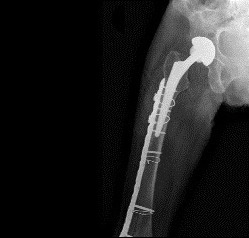

En cas de chute postopératoire, le patient est exposé à une fracture périprothétique (fig. 3) qui peut entraîner des conséquences dramatiques : nouvelle anes­thésie générale, appui interdit pendant quarante-cinq jours, voire quatre-vingt-dix jours, avec une perte d’autonomie importante et un risque infectieux.